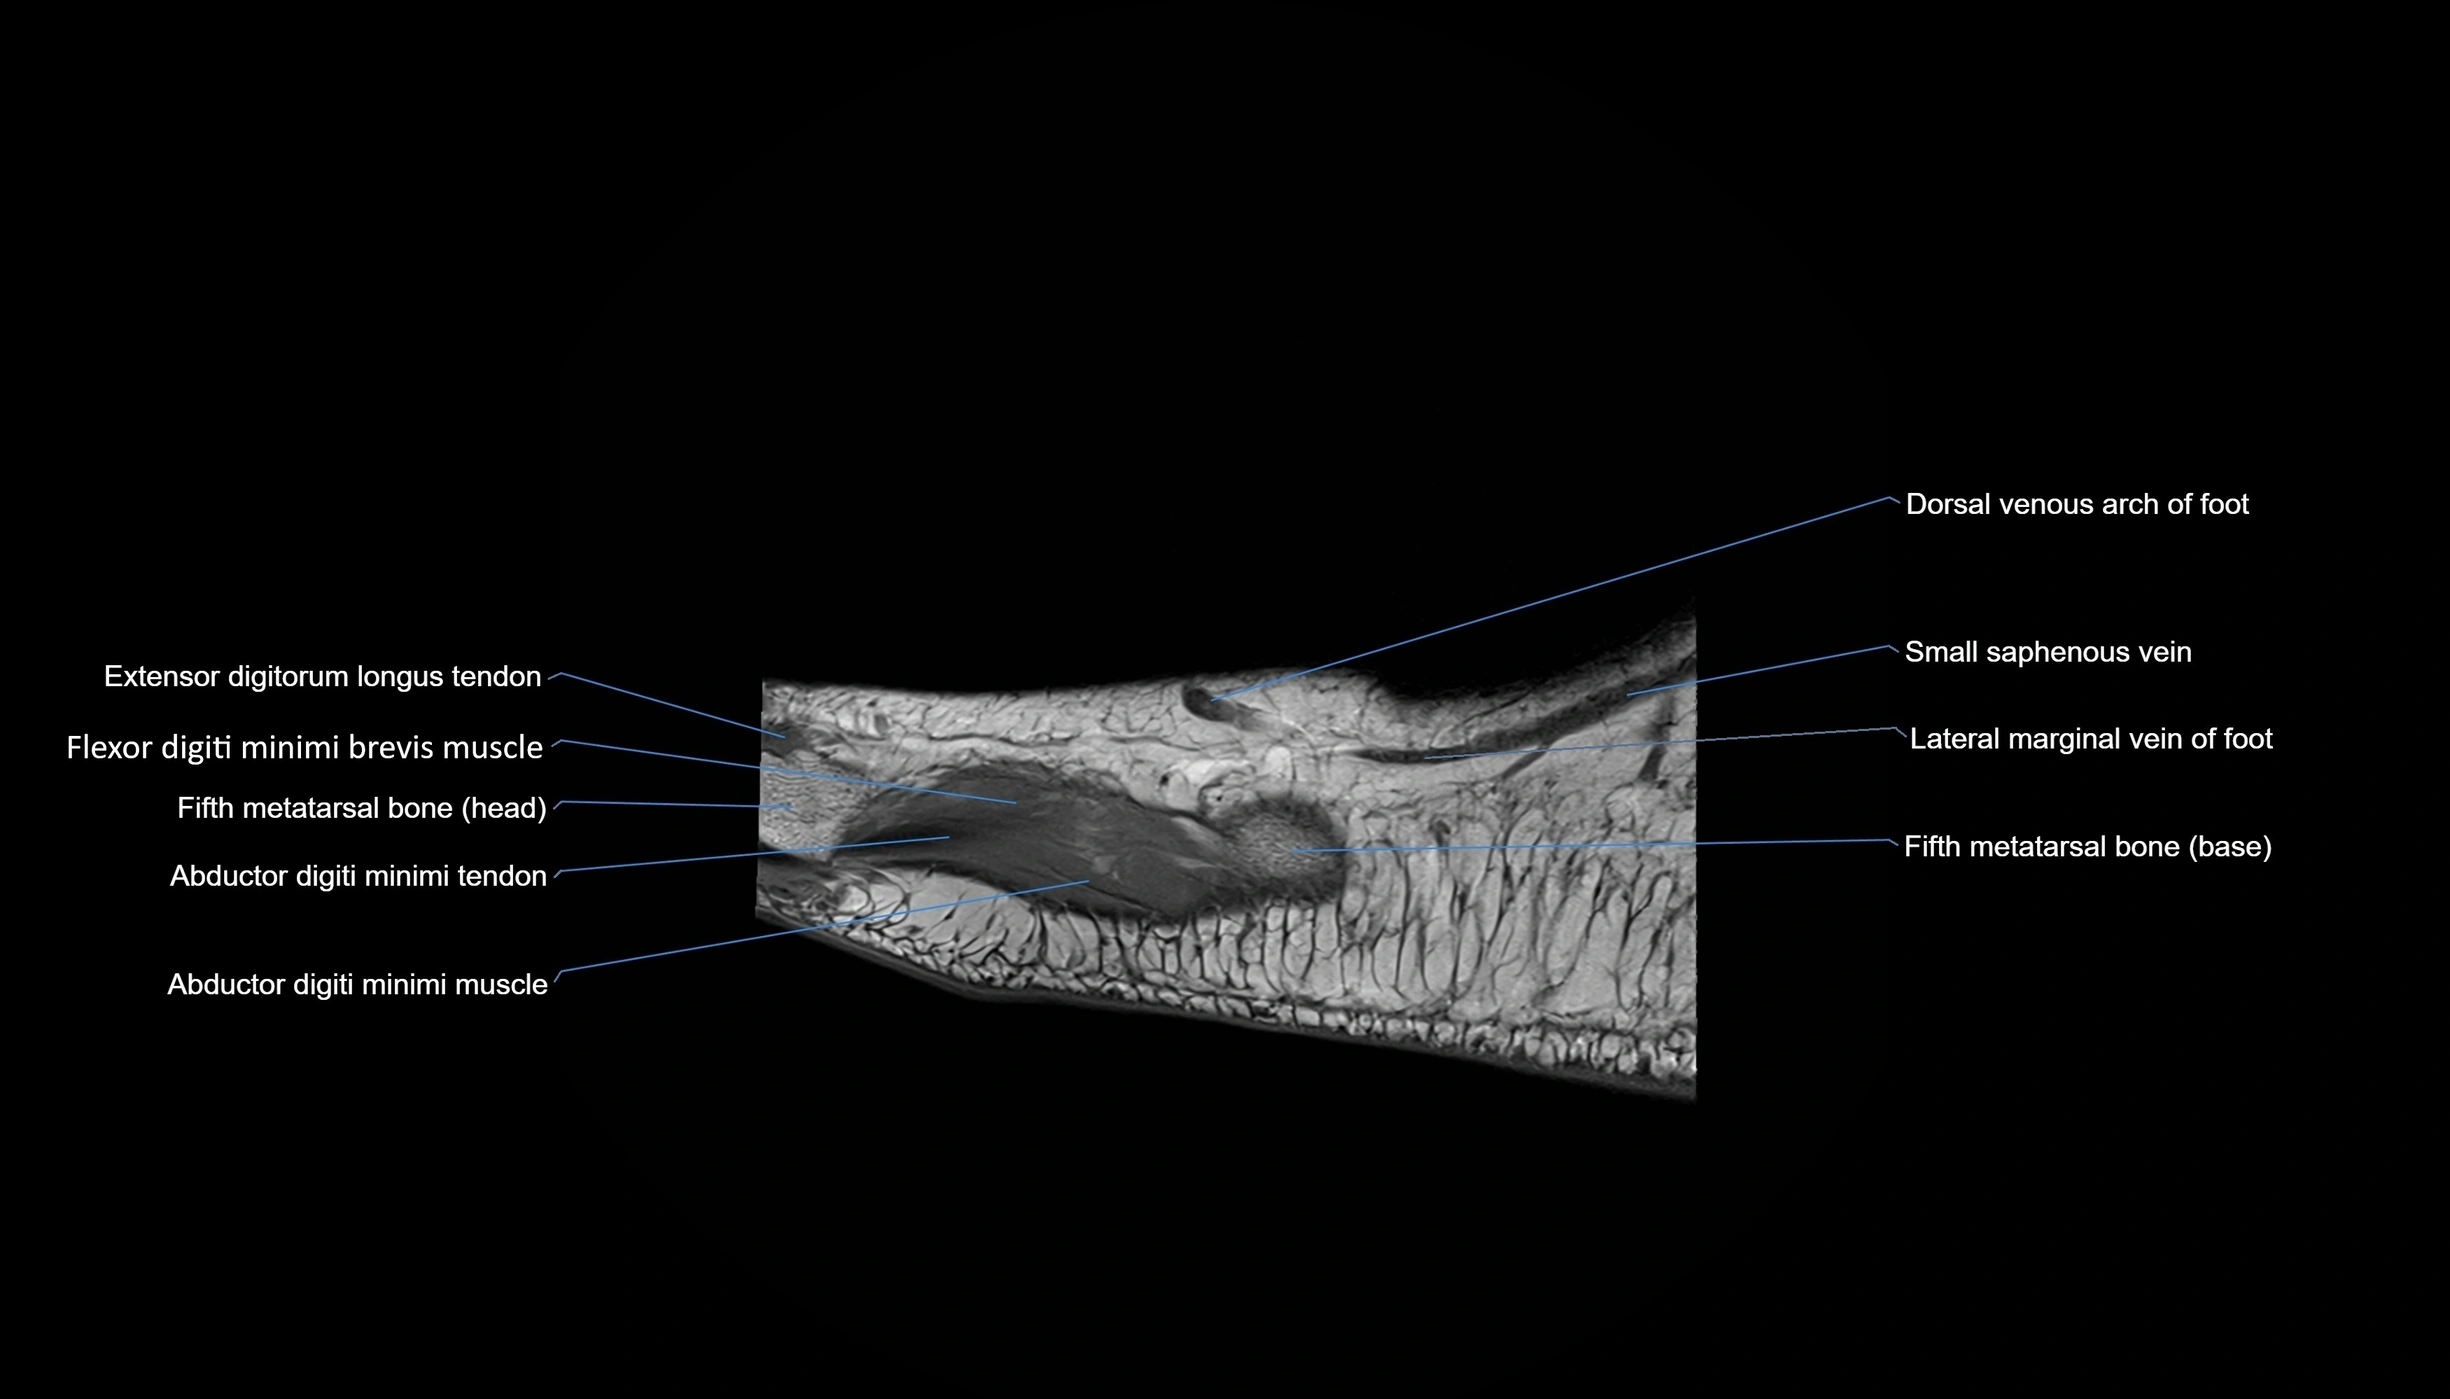

MRI image